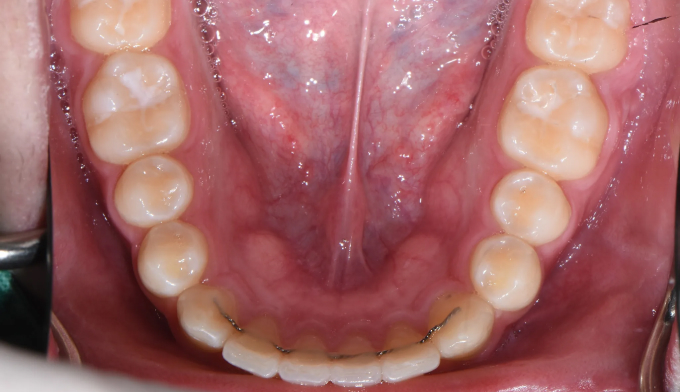

앞니가 돌출되어 있으면서 동시에 위 맨끝 어금니가 아래 어금니와 사선으로 물려있는 가위교합이 관찰됩니다.

가위교합은 음식물 섭취에 있어서도 비효율적이지만, 올바른 잇솔질을 하기가 어려워 구강위생에도 좋지 않아 교정이 필요합니다.

돌출입을 해소하고 동시에 가지런하지 못한 치열을 바르게 펴서 양치하기 좋은 상태로 만들어줍니다.